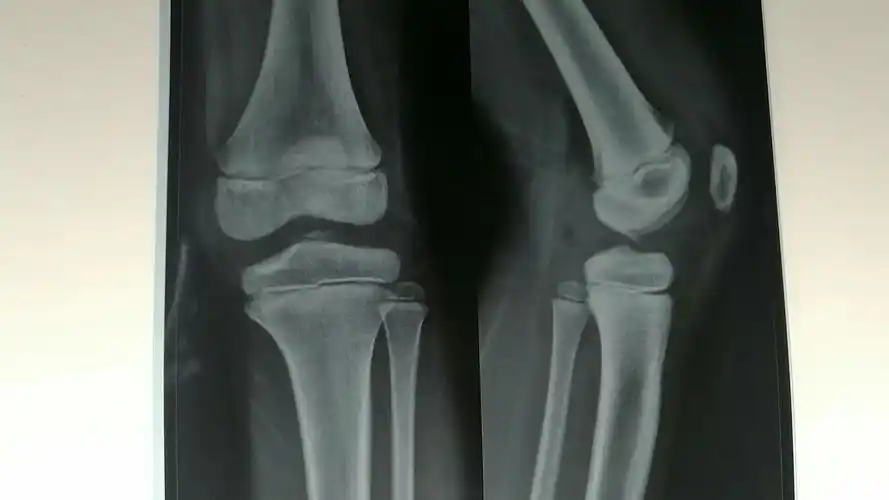

髁间 隆起 内侧髁 胫骨近端各部位名称 外侧髁 胫骨 结节 前面观 后面

窝的外侧壁为外侧髁的内侧面,微凹,其后部为前交叉韧带的附着部;内侧

胫骨平台髁间嵴骨折